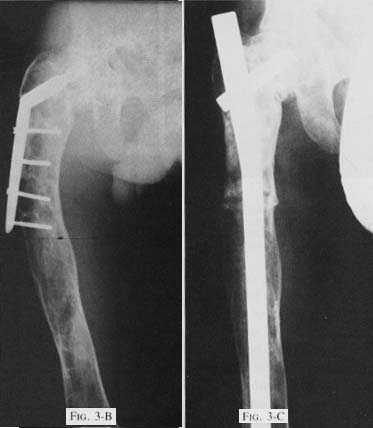

Fig 3-B: Preoperative radiograph showing revision with a compression screw andside-plate with subsequent varus angulation and impending fracture distal to theside-plate.

Fig 3-C: Radiograph made ten months postoperatively demonstratinga slow union at the single osteotomy site.